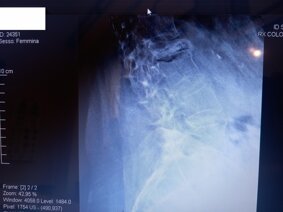

SCHIENA: Rachide toracico